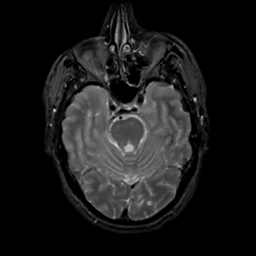

MR Study #8, March 31, 1991 -- Slice #16

[Home][Help][Clinical][Tour 1][Tour 2] Slice 16